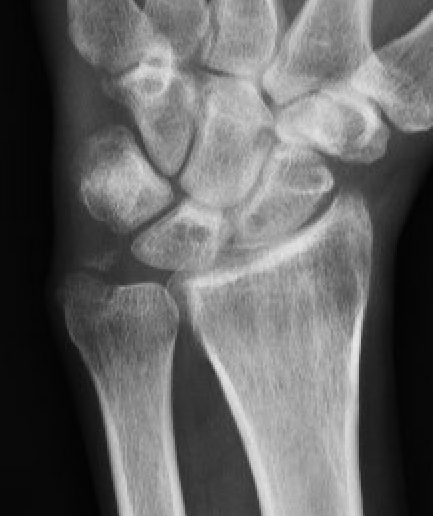

X-ray

Scapholunate gap > 3 mm

AP

| Terry Thomas sign | Cortical ring sign | Scaphoid shortened |

|---|---|---|

|

Increased scapholunate interval > 3 mm compared with other side |

End on view of distal scaphoid due to flexion | Shortened due to flexion |